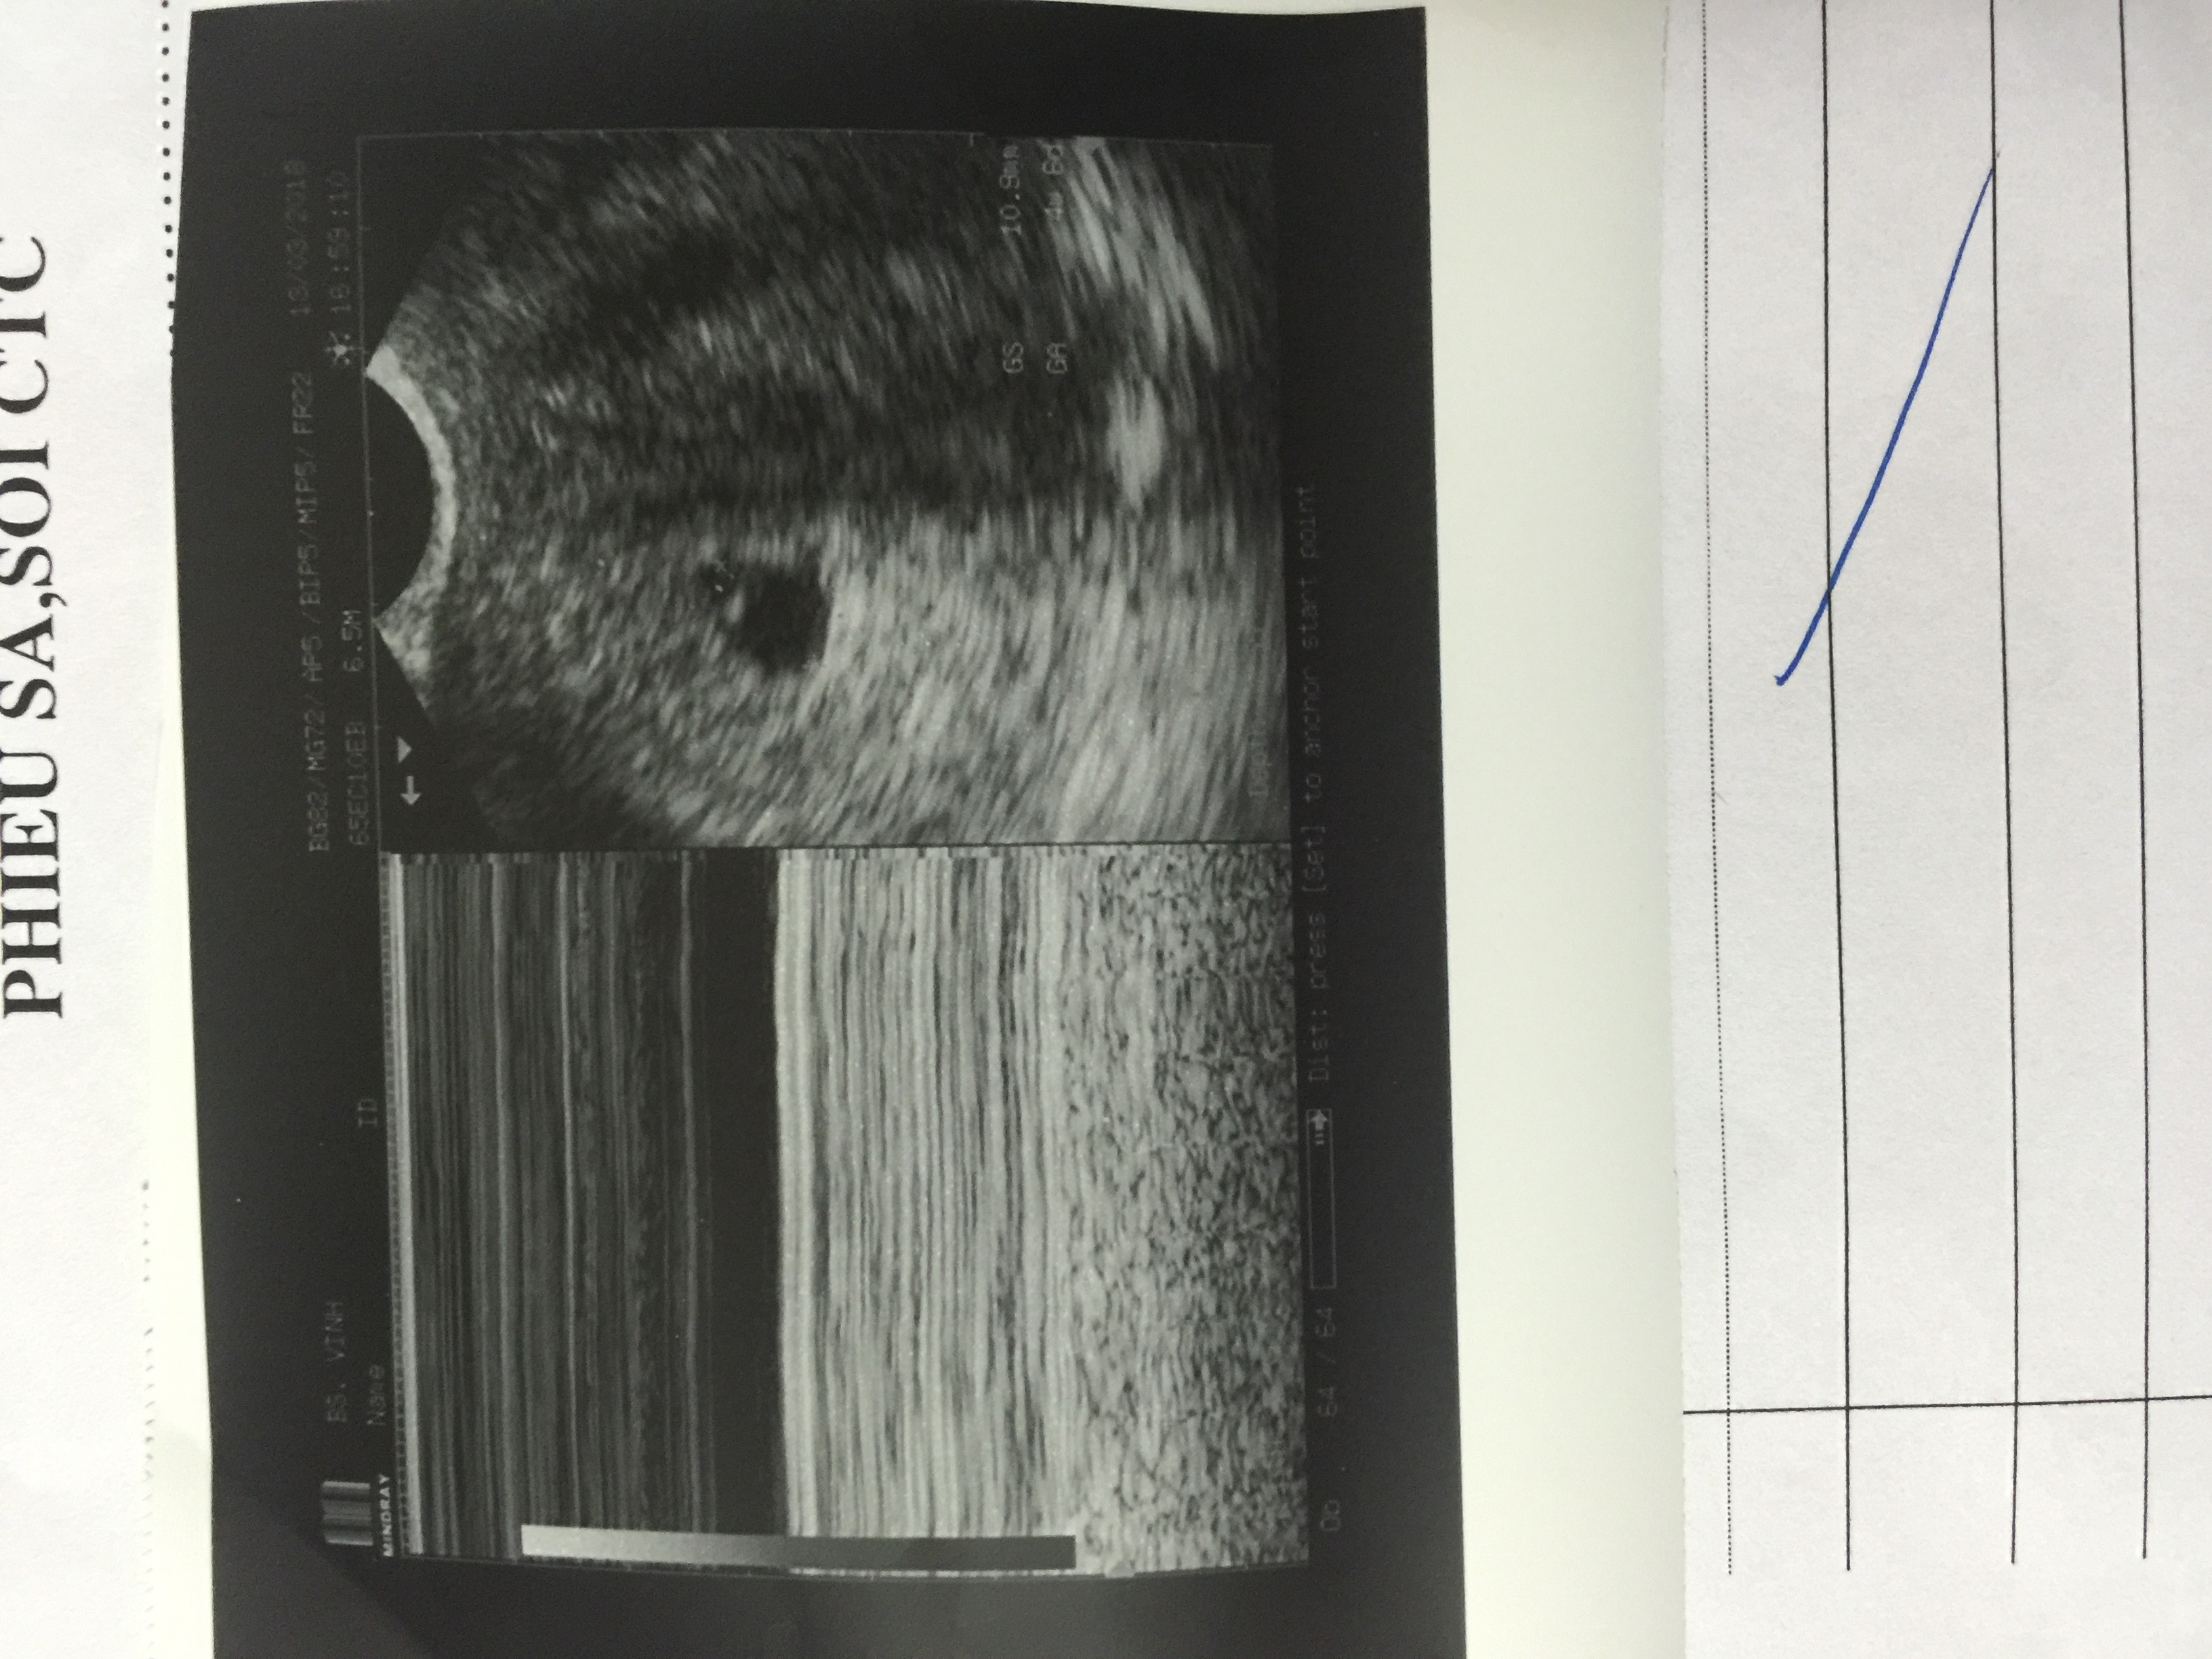

Các bác sỹ giúp em hỏi là thai của em tới nay chưa có tim thai. Doạ sảy em nên dùng thuốc gì ạ. Em tiên Progestone 1 tuần (2 ngày 1 mũi) mà không đỡ. Em bị nhân xơ tử cung 50mm và u tuyến giáp nữa. Các bác sỹ xem giúp em ạ. Em cảm ơn mọi ng nhiều lắm ạ